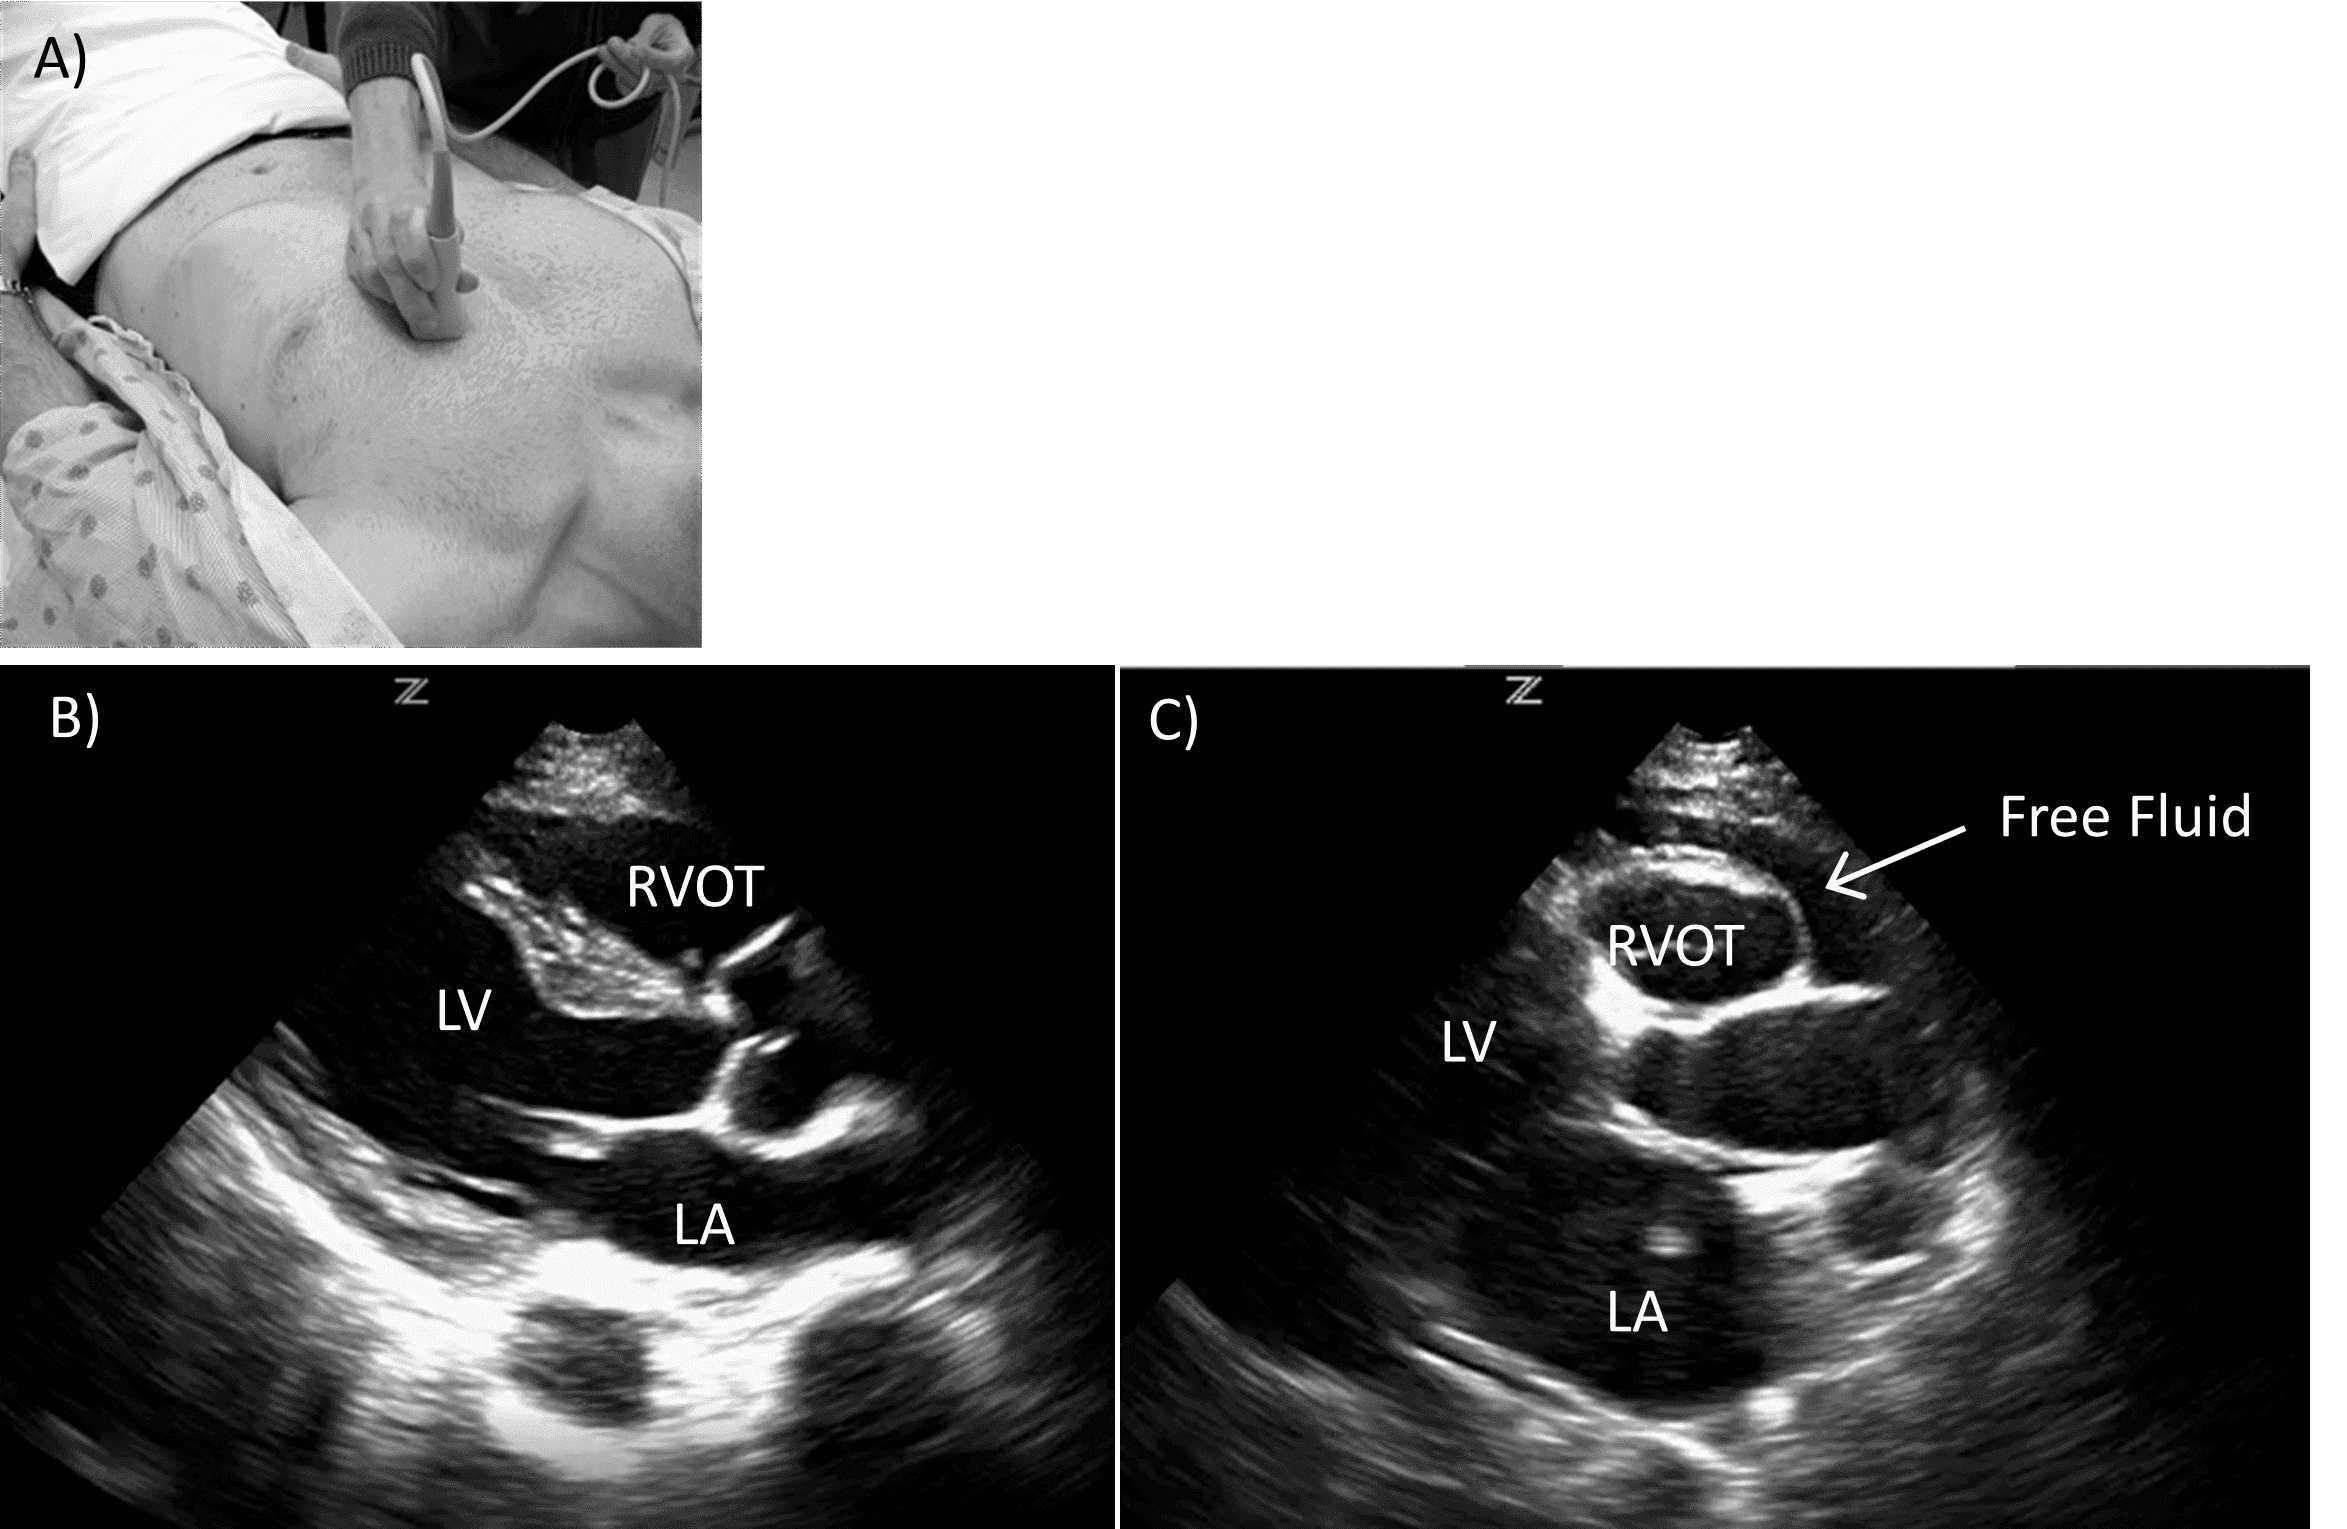

In patients who are obese or those who cannot tolerate significant epigastric pressure, parasternal long or apical four chamber views may be used. The parasternal long view is obtained by placing the probe perpendicularly at the 4th or 5th intercostal space to the left of the sternum with the probe indicator facing the patient’s right shoulder or left hip, depending on user preference. This allows for visualization of the right ventricle, intraventricular septum, left ventricle, left atrium and descending aorta. The right atrium is not visualized (Figure 3).

Parasternal long cardiac view.

A) Probe positioning. B) Normal view. C) Positive view with pericardial effusion.

RVOT (right ventricular outflow tract), LA (left atrium), LV (left ventricle)